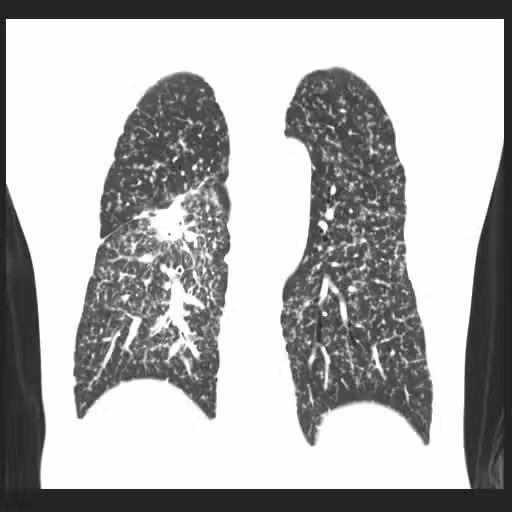

圖片來源:蘇一峰臉書

他建議,病患家屬最好在親人「診斷出肺癌的年齡提前10歲」做篩檢,目前最有效的檢測方式是「低劑量電腦斷層」篩檢,如果肺部乾淨沒有結節,那麼往後3至5年都算安全。另外,蘇一峰也提醒,想要遠離致癌因子,除了油煙、二手煙、空污外,使用家中電器、公司印表機時,也要特別注意...